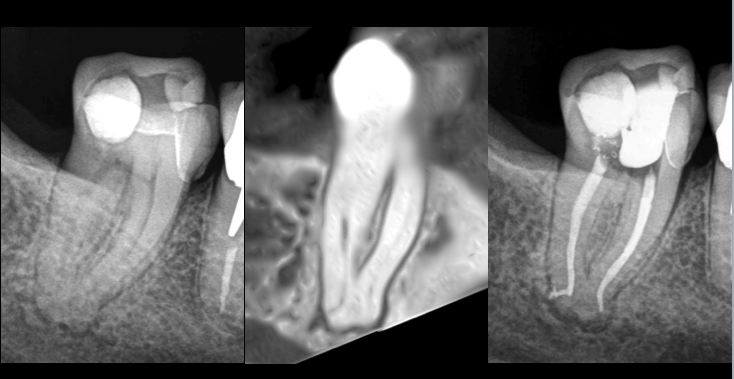

🔎 𝐒𝐮𝐬𝐩𝐢𝐜𝐢𝐨𝐧 𝐝’𝐚𝐧𝐚𝐭𝐨𝐦𝐢𝐞 𝐜𝐨𝐦𝐩𝐥𝐞𝐱𝐞, notamment avec la disparition de l’image canalaire en distal dans le 𝟏/𝟑 𝐚𝐩𝐢𝐜𝐚𝐥.

📸 𝐋’𝐚𝐧𝐚𝐥𝐲𝐬𝐞 𝐂𝐨𝐧𝐞 𝐁𝐞𝐚𝐦 permet d’anticiper ce qu’il se passe en 3D.